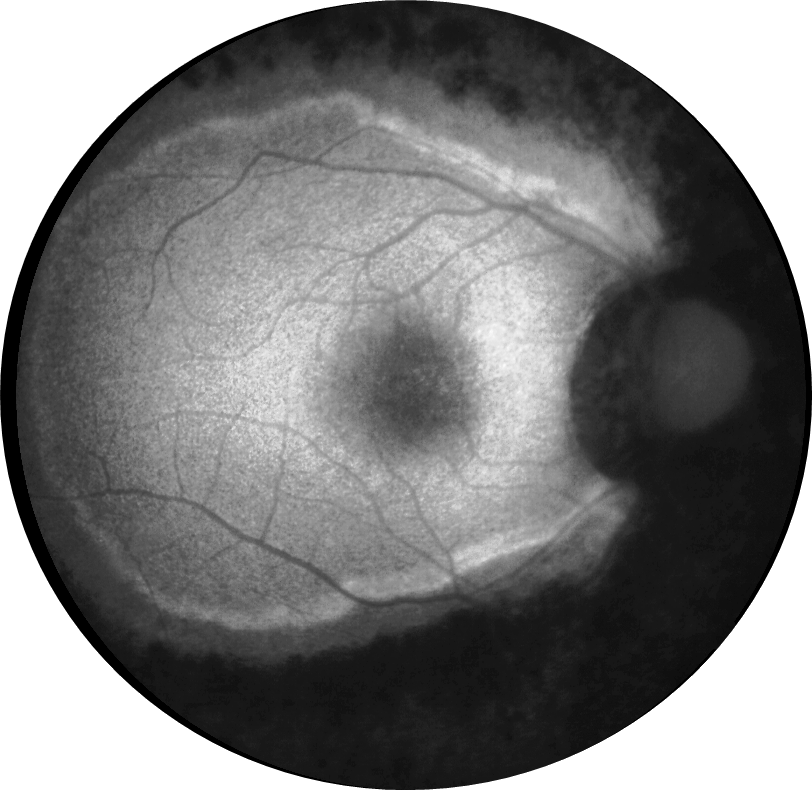

Kliniğimize her iki gözde çocuk yaştan bu yana gittikçe artan görme azlığı şikayetiyle 29 ve 21 yaşındaki iki kardeş başvurmuştur. 29 yaşındaki kardeşin her iki gözde görme keskinliği 3 mps düzeyinde iken 21 yaşındaki kardeşin 0,2 düzeyindedir. Hastaların her iki göz fundus otofloresans görüntülerini görmektesiniz. Bu bulgulara göre tanınız nedir? Lütfen cevabınızı aşağıya yazınız.

Bu ay size her iki gözde çocuk yaştan bu yana gittikçe artan görme azlığı şikayeti olan 29 ve 21 yaşındaki iki kardeşin fundus otofloresans görüntüleri eşliğinde tanılarını sormuştuk.

Tanı: Retinitis pigmentosa ’dır.

Retinitis pigmentosa (RP), tipik olarak orta-periferde başlayıp makula ve foveaya doğru ilerleyen, retinanın ilerleyici dejenerasyonunu içeren bir hastalık sınıfıdır. Tipik semptomlar arasında gece körlüğü, ardından görme alanının azalması, tünel görüşüne ve sonunda yasal körlüğe veya birçok durumda tam körlüğe yol açması yer alır. Retinitis pigmentoza (RP) yaklaşık olarak her 4000 kişiden birinde teşhis edilmektedir ve dünyada en sık görülen kalıtsal retina hastalıklarından biridir. Rod fotoreseptörlerin dejenerasyonu ile karakterizedir.

RP hastalarında, otofloresan görüntülemede zamanla daralan ve hastalık ilerlemesinin bir belirteci olarak hareket eden bir hiperotofloresan halka ortaya çıkabilmektedir. Bu halkanın dış sınırının içindeki fotoreseptöre atfedilen katmanların nispeten korunduğu, halkanın dış sınırının dışında ise elipsoid bölge ve dış limitan membran kaybı ile fotoreseptör katmanlarının incelmesi ve dış nükleer katmanın incelmesi veya yokluğu gözlemlenebilmektedir.